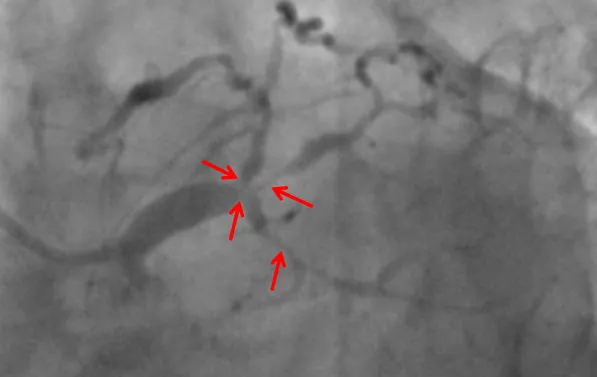

近日,老虎机app (简称老虎机app )心血管内科联合重症医学科、心胸外科等科室,在ECMO器械辅助下,为一名复杂高危冠脉病变患者进行了精准冠脉介入治疗,开通病变冠脉血管。目前患者已康复出院。该项技术的开展,标志我院对高危复杂患者治疗技术又迈上一个新台阶。患者“心悬一线”辗转多家医院就医无果据了解,69岁的张先生(化名)一年来总是感觉胸口闷胀不适,尤其是上楼、快步...